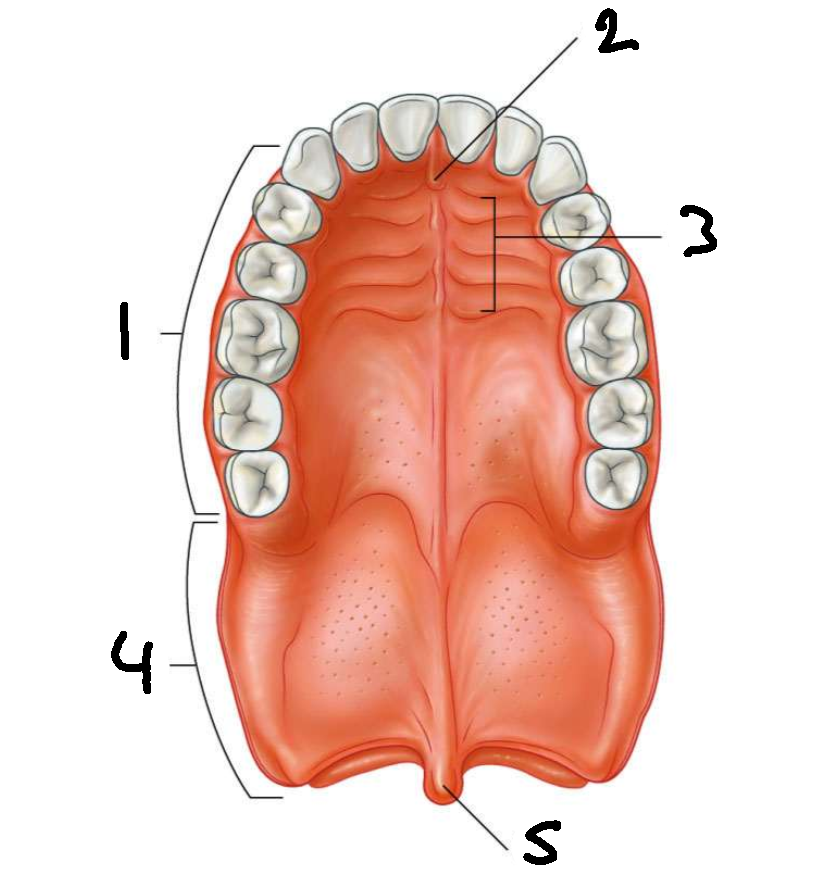

What is 1?

hard palate

What is 2?

incisive papilla

What is 3?

palatine rugae

What is 4?

soft palate

What is 5?

uvula